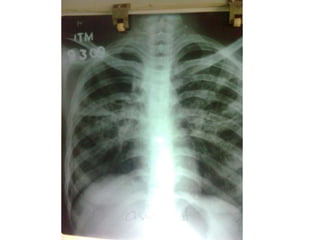

cxr

TRC Opinion(30/9/08): 	          Sputum AFB repeat neg; Sputum C/s for TB taken. Even though pt is sputum AFB negative with symptoms of  TB with  increasing infiltrates in CXR advice to con ATT-CatII Even after all these treatment measures pt continued with fever but breathlessness,Cough and expectoration subsided.pt advised to continue cat-II ATT until c&sreport arrives.